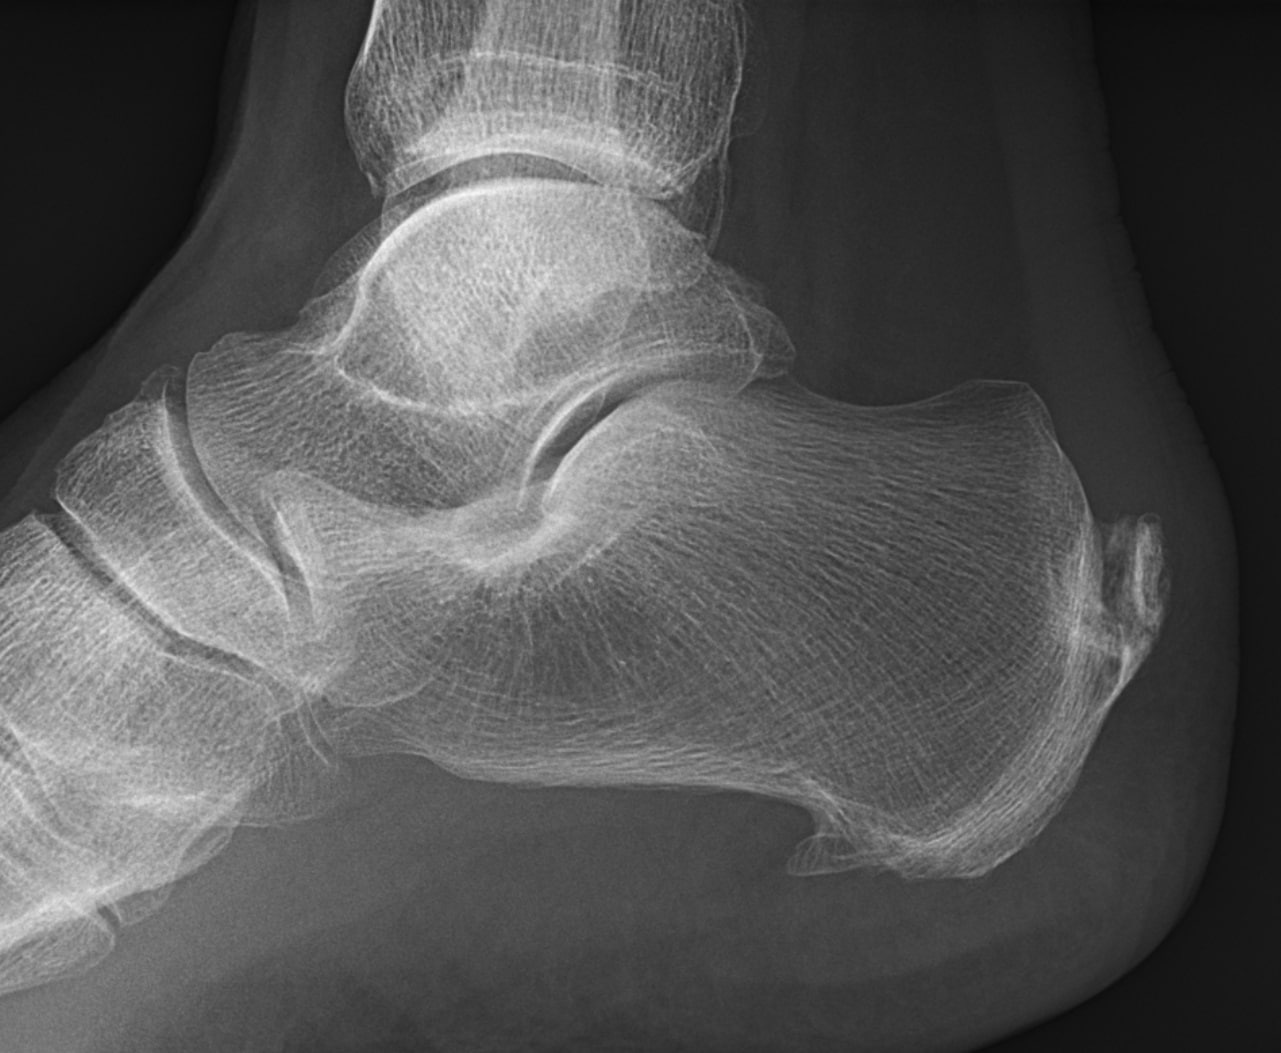

Dallas Heel Spur Specialist

If you have a heel bone spur that is hindering your mobility or quality of life, visit SPORT Orthopedics to find out your treatment options. Our experienced orthopedic specialists will perform a diagnosis, talk through your options, and recommend a treatment plan for your specific situation. Call (469) 200-2832 to schedule your appointment or fill out our online intake form.